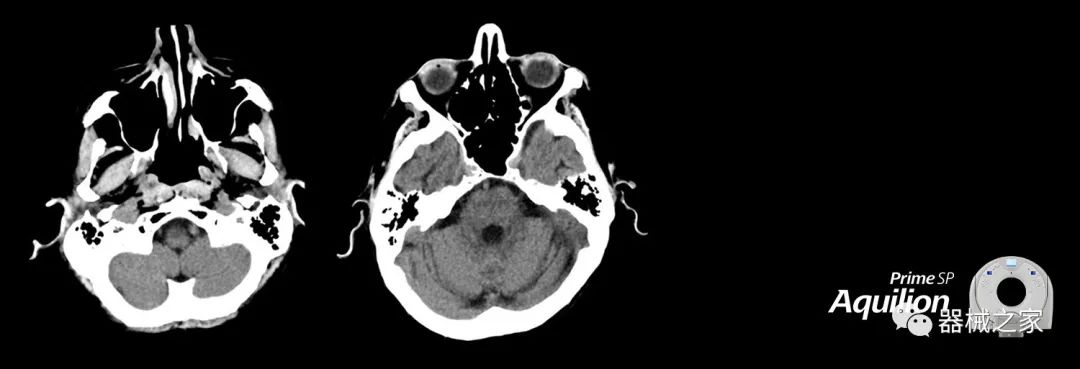

在以患者為中心的放射腫瘤學(xué)領(lǐng)域,計(jì)算機(jī)斷層掃描(CT)的可訪問性,可重復(fù)性和靈活性至關(guān)重要。為了建立這些價(jià)值,佳能醫(yī)療系統(tǒng)美國(guó)公司現(xiàn)在正在擴(kuò)大其放射腫瘤學(xué)CT模擬產(chǎn)品,包括Aquilion Prime SP和Aquilion Lightning 80高級(jí)CT系統(tǒng)。除了Aquilion LB之外,Aquilion Prime SP和Aquilion Lightning 80現(xiàn)在還包括放射治療(RT)選項(xiàng),可為腫瘤學(xué)規(guī)劃提供高質(zhì)量的CT成像和精密工具。

Aquilion Prime SP使設(shè)施能夠處理具有挑戰(zhàn)性的案例,同時(shí)為員工提供快速,靈活和高效的解決方案。

兩個(gè)CT系統(tǒng)均采用0.5 mm x 80排PUREViSION探測(cè)器技術(shù)(可配置并從80-160現(xiàn)場(chǎng)升級(jí)),78 cm孔徑,50 cm視野,AIDR(自適應(yīng)迭代劑量減少)3-D和SEMAR(單個(gè))能量金屬神器減少)技術(shù)。